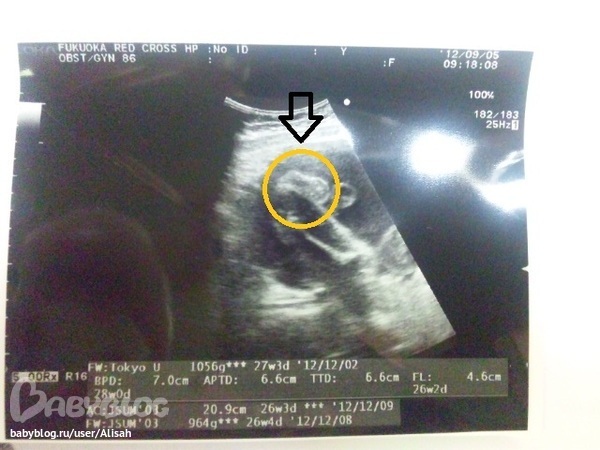

А вот и снимок узи, на котором можно разглядеть нашу пипочку))))

Спасибо!))) У нас тоже по плану - в Японии раз в месяц наблюдают и каждый раз УЗИ делают. Сейчас 27-я неделя, вес - 1056г (там на фото чуть выше), а вот цифра 964 неизвестного происхождения))) А на 23-й неделе вес был 589г., рост, к сожалению, не замеряли. По весу вроде по норме идем)))